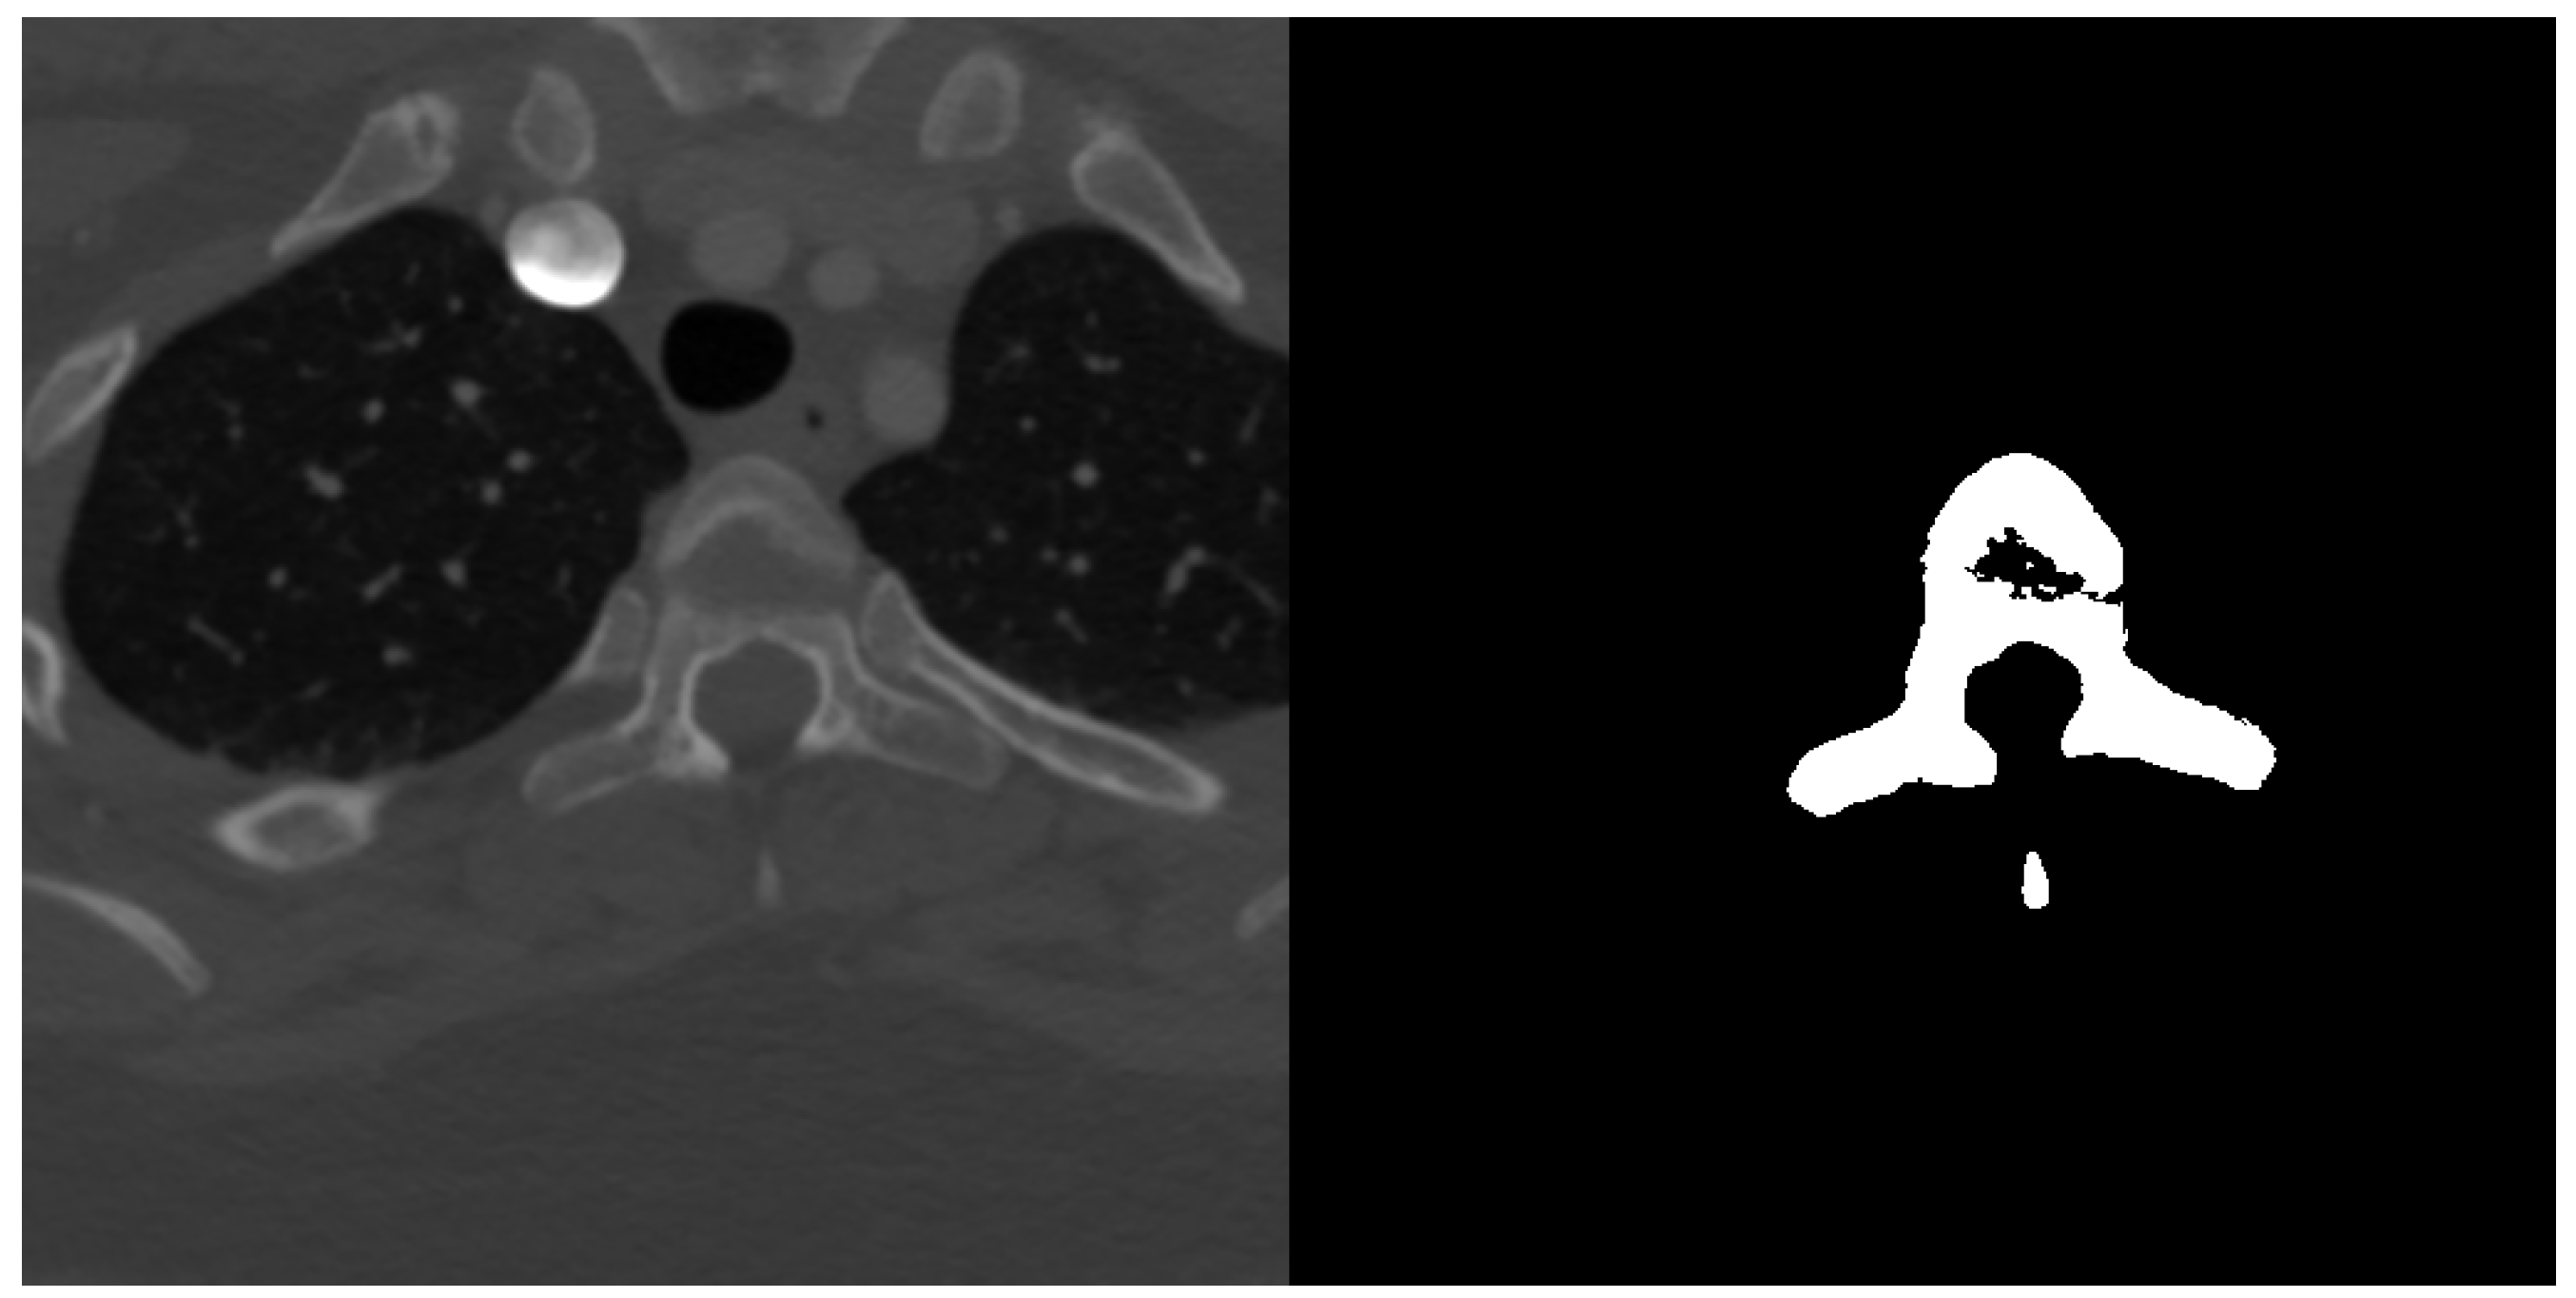

Spine dataset consists of 10 CT scans of different patients in the age 16–35 years old. The pictures had resolution pixels and were provided in NRRD format. Number of slices in each scan was in range from 520 to 600 slices in the third dimension. Scans cover lumbar and thoracic spine region and were acquired without intravenous contrast. Slice thickness is 1 mm per slice and the in-plane resolution is between 0.31 and 0.45 mm. The data have been acquired at the Department of Radiological Sciences, University of California, Irvine, School of Medicine and scanners used include Philips or Siemens multidetector. Data were published as a part of 2014 CSI workshop challenge of the web http://spineweb.digitalimaginggroup.ca. Dataset can be used for development, training and evaluation of spine segmentation algorithms. Image data are provided in NRRD format. An example image slice and according ground truth mask can be seen in Figure 3.

Figure 3.

Example transversal image slice from spine dataset (left) with according ground truth mask (right).